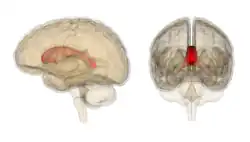

![]() Corpus callosum from above, front part at the top of the image | |

![]() Sagittal section of a brain, front part to the left. The corpus callosum can be seen in the center, in light gray | |

The corpus callosum (Latin for "tough body"), also callosal commissure, is a wide, thick nerve tract, consisting of a flat bundle of commissural fibers, beneath the cerebral cortex in the brain. The corpus callosum is only found in placental mammals.[1] It spans part of the longitudinal fissure, connecting the left and right cerebral hemispheres, enabling communication between them. It is the largest white matter structure in the human brain, about 10 cm (3.9 in) in length and consisting of 200–300 million axonal projections.[2][3]

A number of separate nerve tracts, classed as subregions of the corpus callosum, connect different parts of the hemispheres. The main ones are known as the genu, the rostrum, the trunk or body, and the splenium.[4]

The corpus callosum forms the floor of the longitudinal fissure that separates the two cerebral hemispheres. Part of the corpus callosum forms the roof of the lateral ventricles.[5]

The corpus callosum has four main parts – individual nerve tracts that connect different parts of the hemispheres. These are the rostrum, the genu, the trunk or body, and the splenium.[4] Fibres from the trunk and the splenium, known together as the tapetum ("carpet"), form the roof of each lateral ventricle.[6]

The front part of the corpus callosum, towards the frontal lobes, is called the genu ("knee"). The genu curves downward and backward in front of the septum pellucidum, diminishing greatly in thickness. The lower, much thinner part is the rostrum and is connected below with the lamina terminalis, which stretches from the interventricular foramina to the recess at the base of the optic stalk. The rostrum is named for its resemblance to a bird's beak.

The end part of the corpus callosum, towards the cerebellum, is called the splenium. This is the thickest part, and overlaps the tela choroidea of the third ventricle and the midbrain, and ends in a thick, convex, free border. Splenium translates as "bandage" in Greek.

The trunk of the corpus callosum lies between the splenium and the genu.